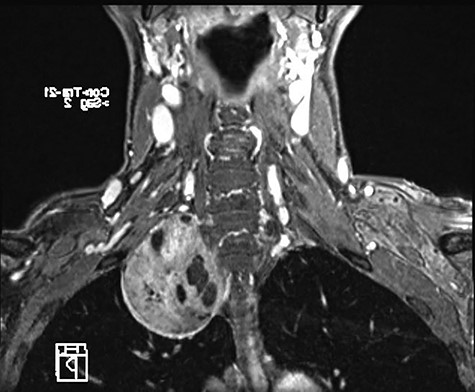

A 58-year-old female smoker with a history of cosmetic surgery complained of a large supraclavicular cervical mass associated with some neurological disorders (including anisocoria and ptosis of the right eyelid) since 2014. An ultrasound of the neck with cytological examination raised the suspicion of ‘Schwannoma’ with liquid content. Computed tomography (CT) of the neck and chest confirmed the presence of a 6.6 × 6 cm paracervical and paramediastinal right mass that dislocated the trachea and esophagus. The injury was also confirmed by nuclear magnetic resonance imaging (MRI) of the neck and chest (Figs 1, 2).

MRI of paracervical neurinoma in the coronal projection affecting the right paravertebral structures.